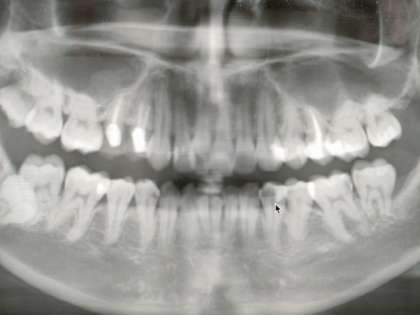

人間の噛む力はどれぐらいでしょうか?

(体重が60kgの人の場合で考えてください)

歯がきちんとそろっていれば、その人の体重と同じぐらいの重さまで噛む力を出すことができるそうです。